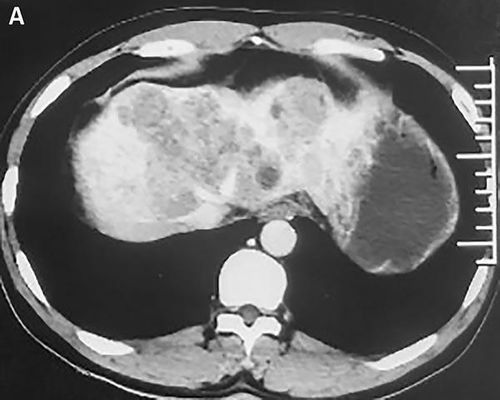

诊断手段:为提高确诊率,依赖影像学检查结合血清标志物的检测是关键。MRI等现代影像技术在此类疾病的诊断中发挥着重要作用。